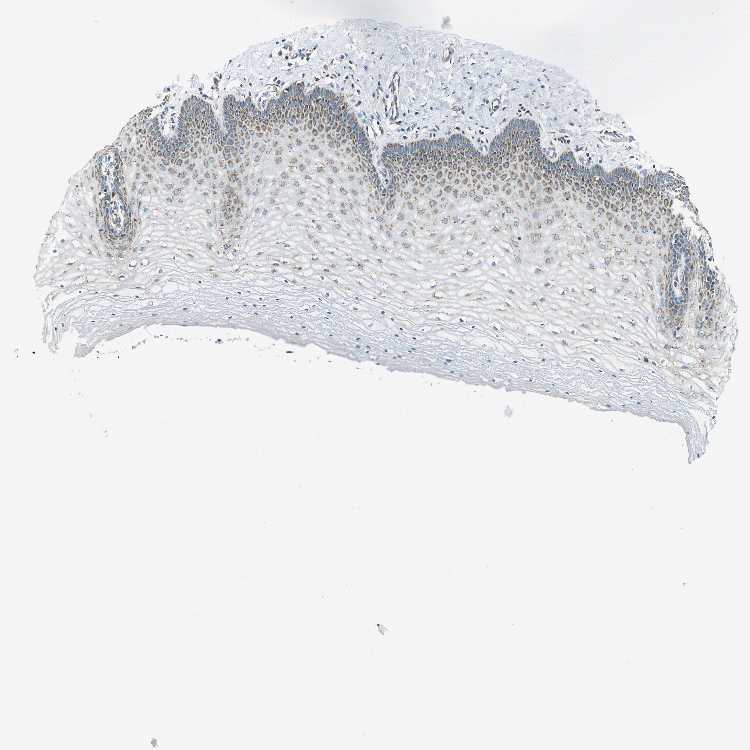

CERVIX - Antibody stainingi

Antibody staining in the annotated cell types in the current human tissue is reported as not detected, low, medium, or high, based on conventional immunohistochemistry profiling in selected tissues. This score is based on the combination of the staining intensity and fraction of stained cells.

Each image is clickable and will lead to virtual microscopy that enables deeper exploration of all samples and also displays staining intensity scores, fraction scores and subcellular localization as well as patient and tissue information for each sample.

Antibody HPA004895Antibody CAB013018

Glandular cells LowMedium

Squamous epithelial cells -Medium